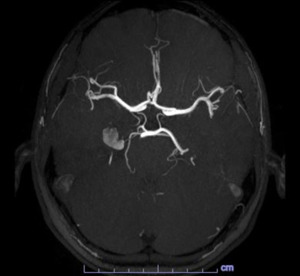

With the diagnosis not clear, an MRA with contrast was obtained the next day which revealed a 1.2 cm lesion involving the medial right temporal lobe, the radiologist favored a cavernous hemangioma but could not completely rule out an aneurysm as the lesion is very hyperintense on T1-weighted images (figs.5 and 6).